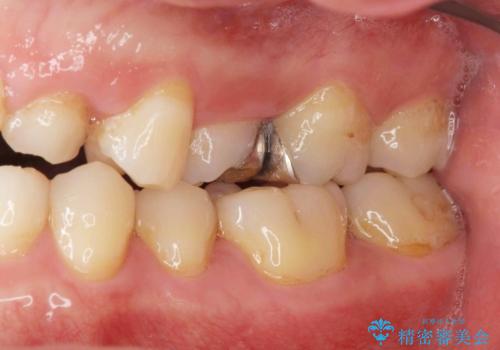

- ねじれてしまっている奥歯の矯正治療、銀歯のセラミック治療を求めて来院されました。

銀歯を外す前に部分矯正治療を行うことで歯のポジションを調整したのち、セラミック治療を行います。

90°ねじれてしまっていた歯を、矯正治療で治し、前後の歯の咬合関係も改善してしっかりと噛めるようになりました。